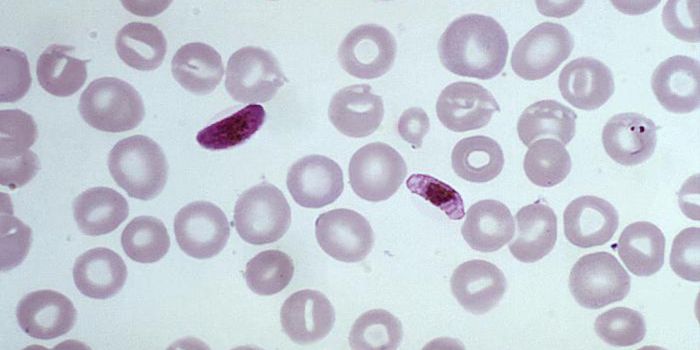

DEC 09, 2022Clinical & Molecular DXMalaria is a mosquito-borne illness that causes flu-like illness and high fevers. Though illness and death from malaria ...